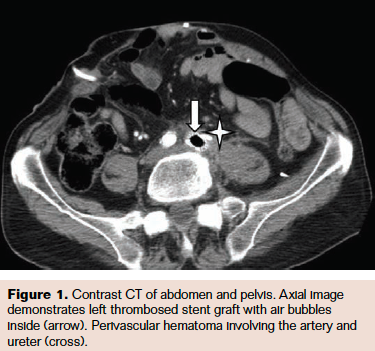

Two years later, the patient underwent computed tomography (CT) to evaluate his ischemic left leg and to facilitate definitive operative planning. CT results revealed thrombosis of his common iliac stent, with an air bubble inside, and a perivascular hematoma involving the left common iliac artery and left ureter.